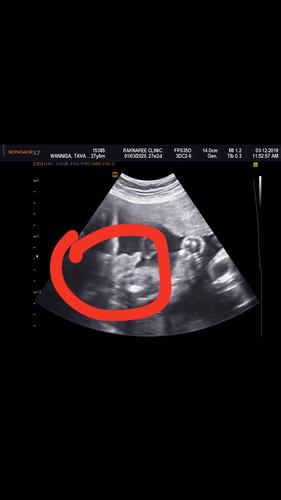

บ้านนี้ซาวที่ร.พ ตอน5เดือนบอกได้ผญ พอวันนี้ไปซาวด์เเบบ4มิติ มี่คลีนิคเห็นจู๋น้อยชัดเลยค่ะ. เเต่ปลื้มค่ะ น้องครบสมบูรณ์ดีค่ะ คุณหมอบอก ปากกระจับจมูกโด่ง. ☺️☺️ปลื้มจังค่ะ

ในภาพซาวที่แม่วงไว้แดงๆ ก็เพศชายนะคะ ตอน5เดือนหรอคะ